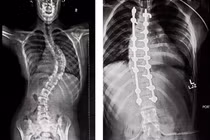

Cột sống, hay còn gọi là xương sống giúp nâng đỡ toàn bộ cơ thể của chúng ta. Được cấu tạo bởi 24 đốt xương và các đĩa đệm, cột sống giúp chúng ta thực hiện các động tác cúi, ngửa, nghiêng và giữa các đĩa đệm có các nhân keo giúp cho cột sống chuyển động uyển chuyển.